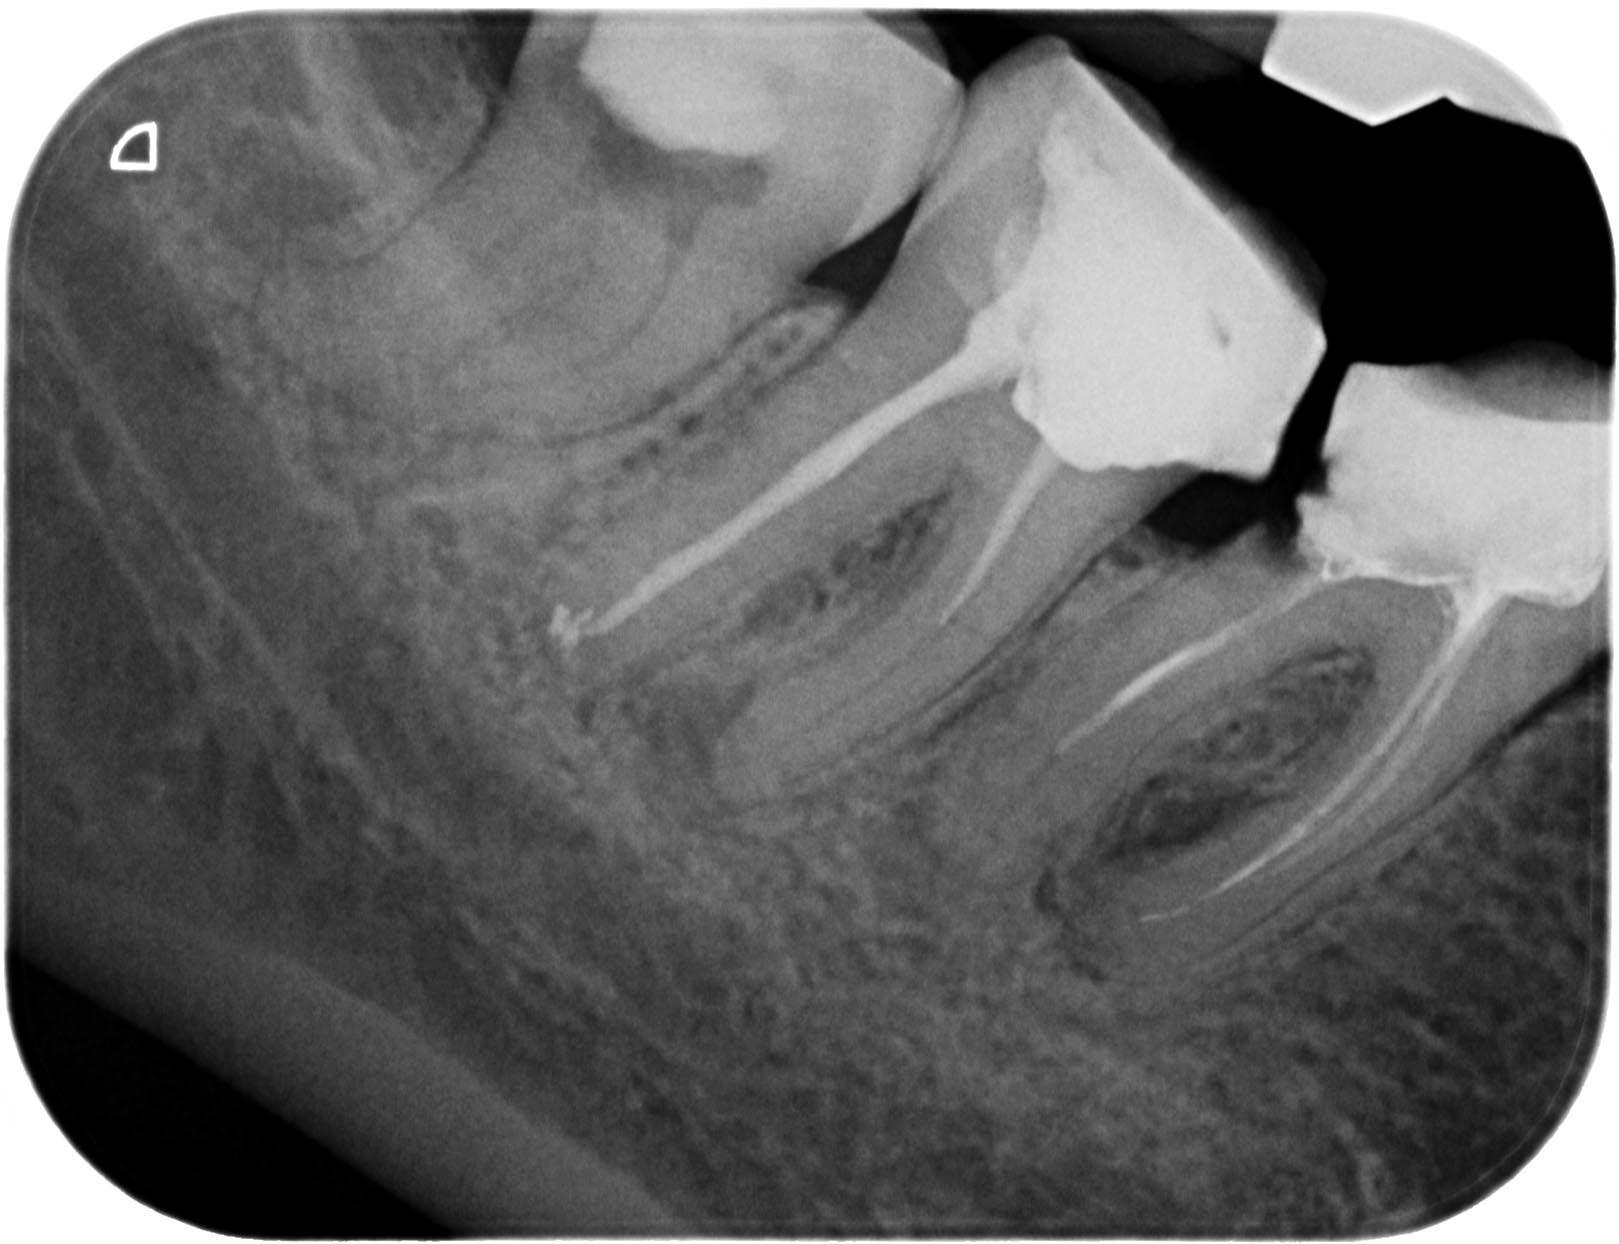

48-1 Veröffentlicht 8. Mai 2011 am 1619 × 1244 in Wurzelkanalbehandlung 48 mit RACE 02, MTwo und VDW Reciproc